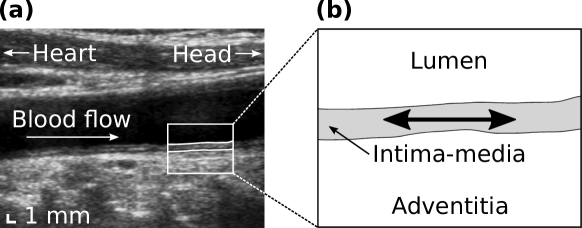

Cardiovascular risk evaluation is a major public health issue as well as a tremendous scientific challenge. In the last recent years, the characterization of the elastic deformation of the tissue layers of the common carotid artery along the direction parallel to the vessel axis during the cardiac cycle in ultrasound sequences (also called cine-loops) has gathered a growing attention. This patho-physiological phenomenon, hereafter dubbed as LOKI for longitudinal kinetics, corresponds to the shear between the intima-media complex and the tunica adventitia (Figure 1persson2003new . This motion was shown to be cyclic and reproducible over several months ahlgren2012different .

Refer to caption

Figure 1: (a) Longitudinal view of a common carotid artery in B-mode ultrasound. (b) Detail of the far wall. The cyclic motion of the tissue layers along the axis of the vessel (i.e., LOKI) is indicated by the double arrow.